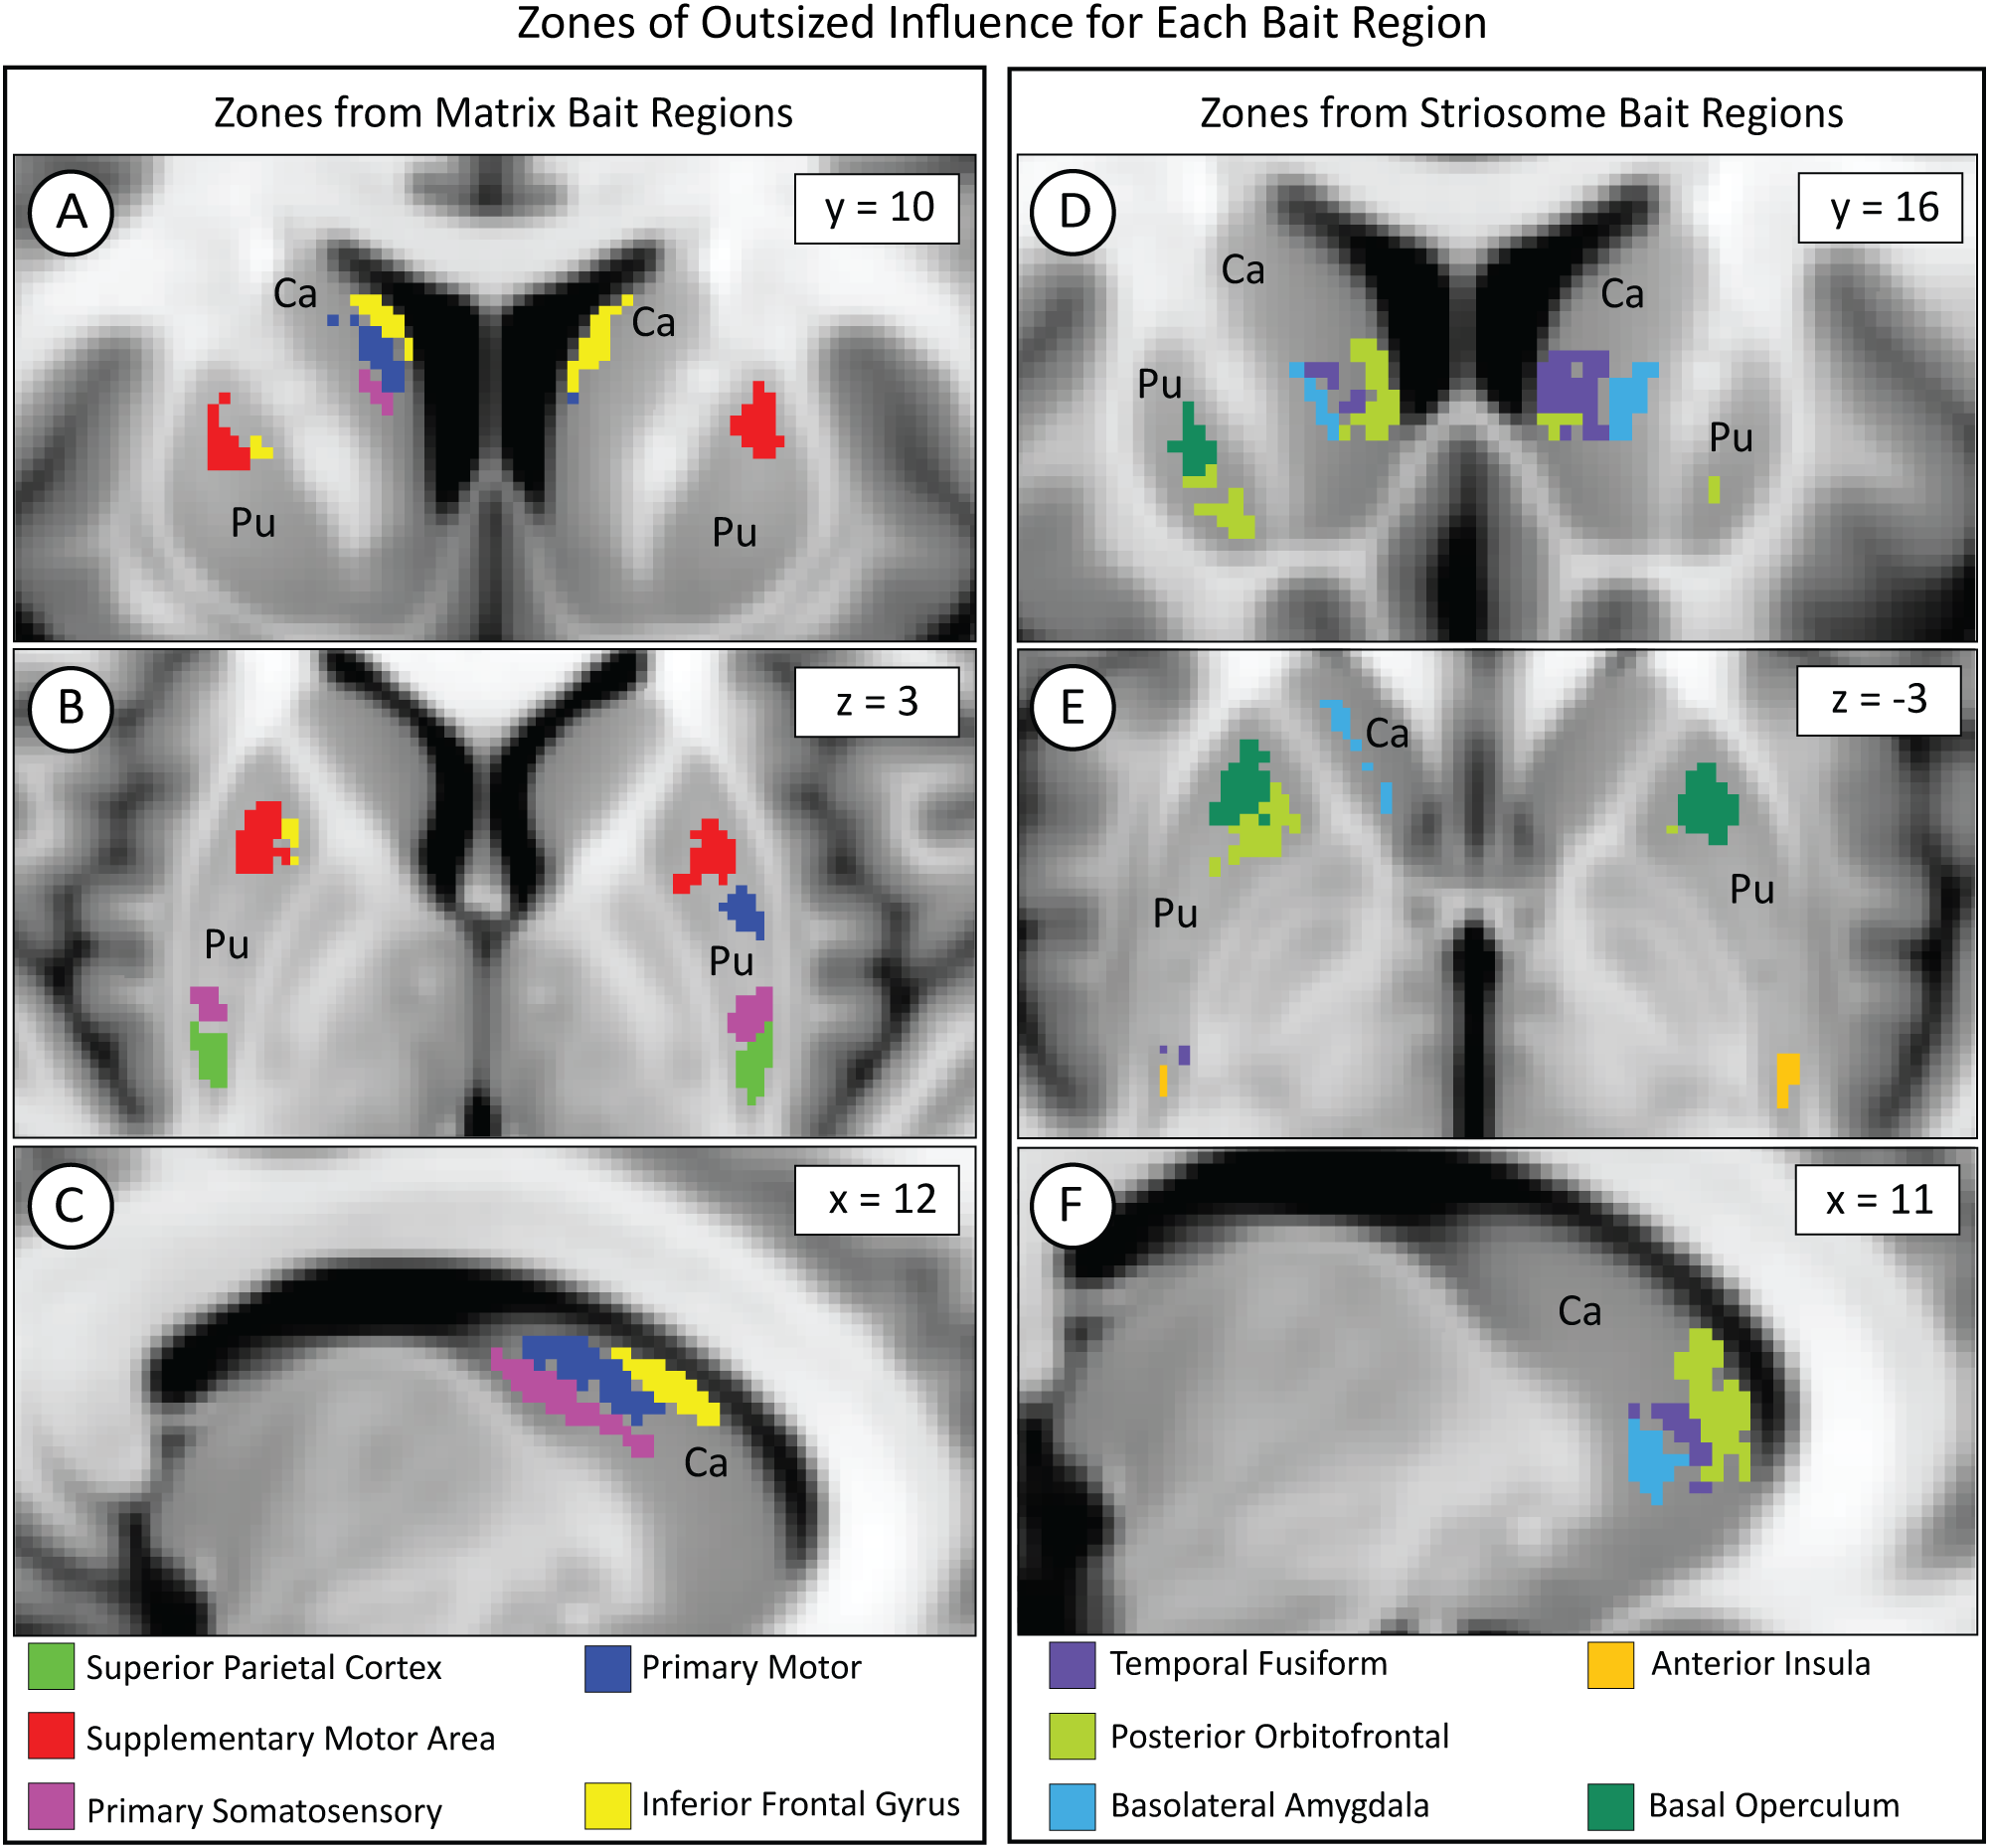

3.9 Somatotopic organization of corticostriate projections

We mapped the locations where each of our 10 bait regions had the greatest influence on compartment-like bias. To identify these somatotopic zones, we parcellated the striatum with nine out of our ten bait regions, leaving one bait region out. We then subtracted this “N-1” parcellation from the original striatal parcellation (which was based on all ten bait regions) to identify the influence of the left-out bait region. Although we parcellated the left and right hemispheres separately, the somatotopic zones attributable to each bait region were highly similar in size and location between hemispheres (Figure 6). Each somatotopic zone was spatially distinct with no overlap between zones. Notably, the somatotopic zones in these subjects are highly similar to the somatotopic zones we previously described in other cohorts (25, 40, 46).

Figure 6

While each bait region projected broadly within the striatum, each region dominated the contribution to compartment-like bias within a discrete somatotopic zone, as seen in the coronal (A, D), axial (B, E), and sagittal (C, F) planes. Zones influenced by matrix-favoring bait regions are shown in (A–C), while zones influenced by striosome-favoring bait regions are shown in (D–F). Zones might border but never overlapped. Although we parcellated the left and right hemispheres independently, the location of each somatotopic zone was highly similar between hemispheres. Visible differences between the hemispheres (e.g., green voxels in D) are largely due to millimeter-scale differences in location (eg, green voxels in E). Pu, putamen; Ca, caudate. The images adhere to radiographic convention. Coordinates follow MNI convention.

We measured matrix-like and striosome-like volume (P≥0.55) within each somatotopic zone (Figure 7). We expressed these volume measures as a normalized ratio of volume change to capture changes in both compartments as a single value: . The dominant compartment refers to matrix-like volume for matrix-favoring bait regions and striosome-like volume for striosome-favoring bait regions.